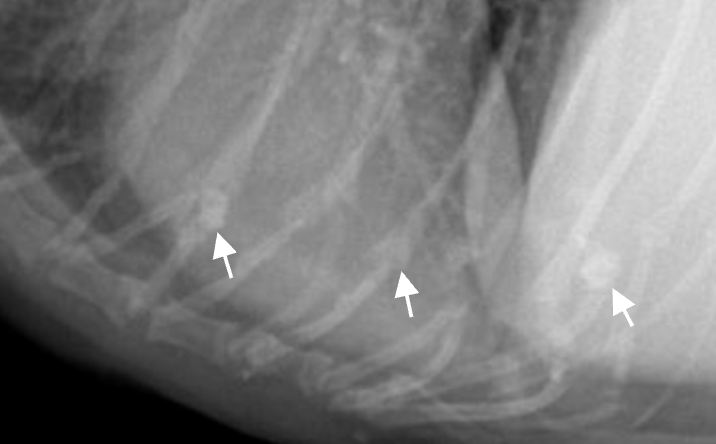

CCJ (costso-chondral junction) ![]() - ํ๊ฒฐ์ ๊ณผ ์ค์ธํ์ง ์๋๋ก. - ๋ฅ์คํํธ์์๋ ๊บพ์ด์ ๊ด์ ํ๊ธฐ ๋๋ฌธ์ ๋ ๋๋๋ฌ์ง. |